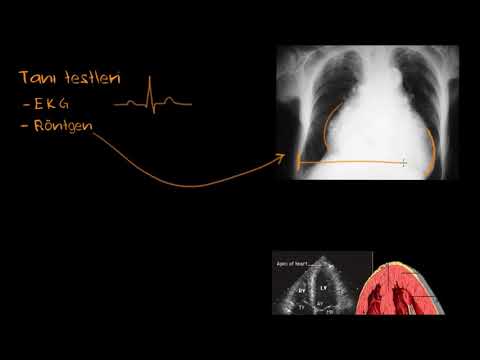

- Kalp Kapak Hastalıkları Tanısı ve Tedavisi TUR

Kalp Kapak Hastalıkları Tanısı ve Tedavisi